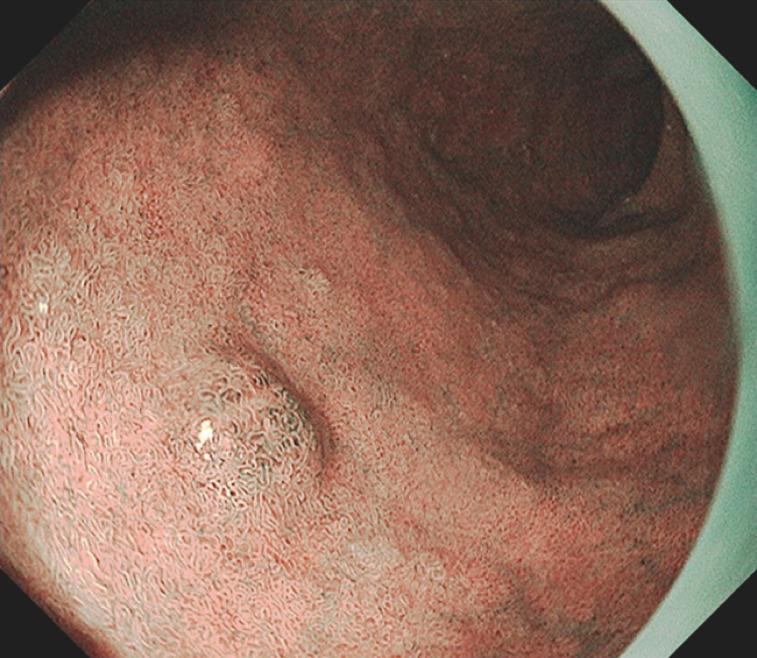

Misidentification of a duodenal neuroendocrine tumor as an adenoma, with subsequent attempted resection by cold snare polypectomy.